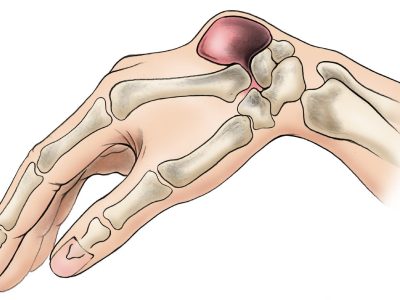

Rephrased Paragraph: A thumb fracture can lead to significant challenges, as impaired thumb function impacts your ability to grip and handle objects effectively. Certain fractures in the thumb are particularly concerning, as they may raise the likelihood of developing arthritis…

A thumb ligament injury occurs when the ligaments that stabilize the thumb are overstretched or torn due to excessive force. This type of injury typically happens when the thumb is forcefully bent backward, away from the palm, often as a…